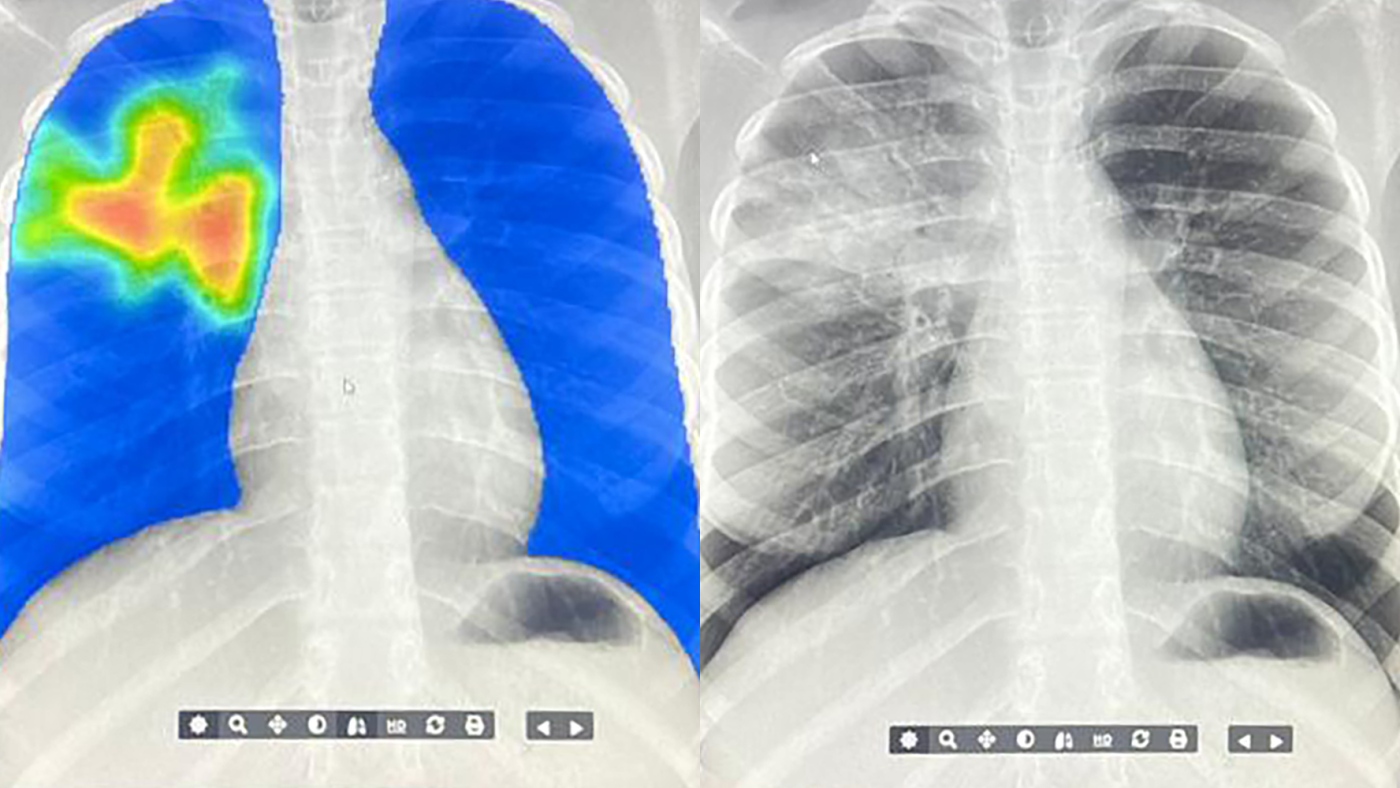

Thank you to @LeciaSequist for leading and organizing this fascinating panel on deploying Sybil in different hospital settings w/ Florian Fintelmann, Raymond Osarogiagbon, @MaryPasquinelli, and Bill Mayfield! #AICures2025